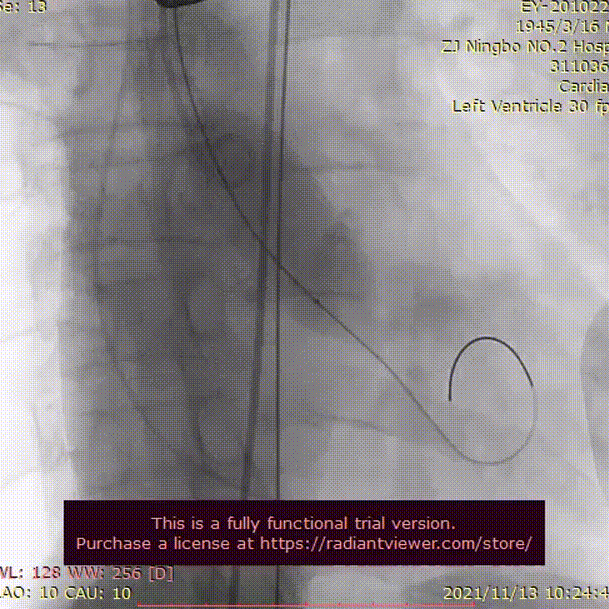

沿导丝送23 mm球囊至主动脉瓣口,定位准确后,在180次/分临时起搏下用球囊扩张狭窄的主动脉瓣,观察造影见大量返流,经过大家讨论后决定退出23mm球囊后再次送入25mm球囊进行预扩,同时观察造影见无返流,冠脉情况良好。后沿导丝送入VenusA-Plus®可回收输送系统L29型号瓣膜缓慢释放,同时确认冠脉情况,植入后经多体位投照和主动脉根部造影,显示瓣膜释放位置满意,瓣膜形态良好。术后未出现并发症,手术取得圆满成功。